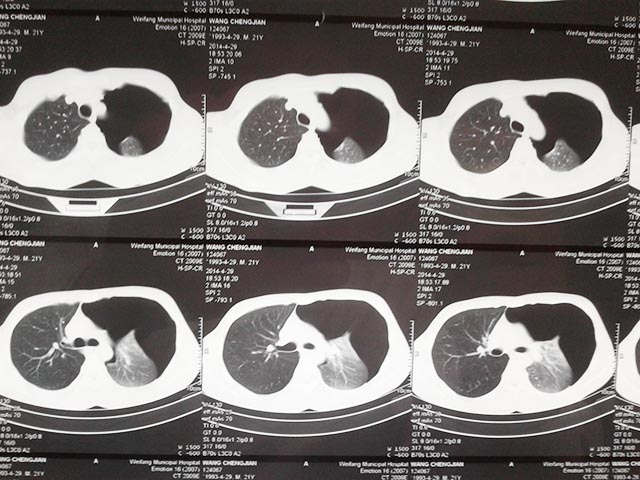

隨即做了胸部CT檢查,發(fā)現(xiàn)左側(cè)肺組織已經(jīng)壓縮了50%,并且雙肺可見(jiàn)多發(fā)彌漫的肺大皰,在與患者及家屬溝通后,先行左側(cè)胸腔閉式引流術(shù),排出了積氣,緩解了癥狀,穩(wěn)定了生命體征。

肺大皰自發(fā)性氣胸手術(shù)前